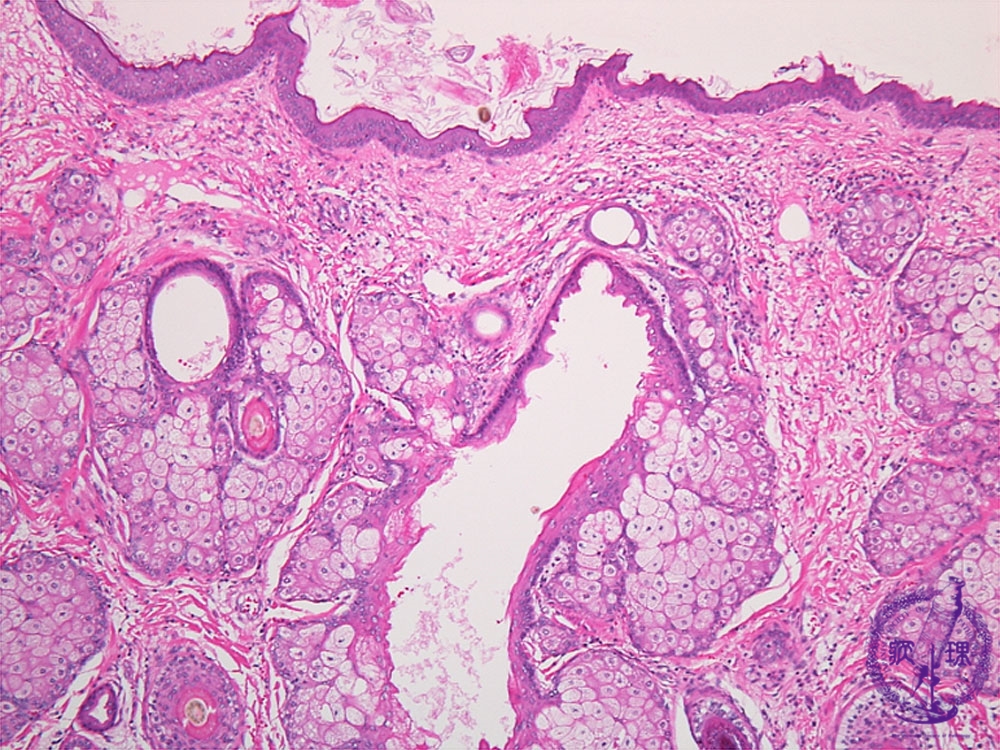

- ★(9)Ovarian teratoma(Dermoid cyst)

Histology (HE stain, low power): Mature cystic teratoma (dermoid cyst). Epidermis (yellow dotted line) or follicles (red dotted line) and sebaceous glands (blue dotted line) as skin appendages are apparent.